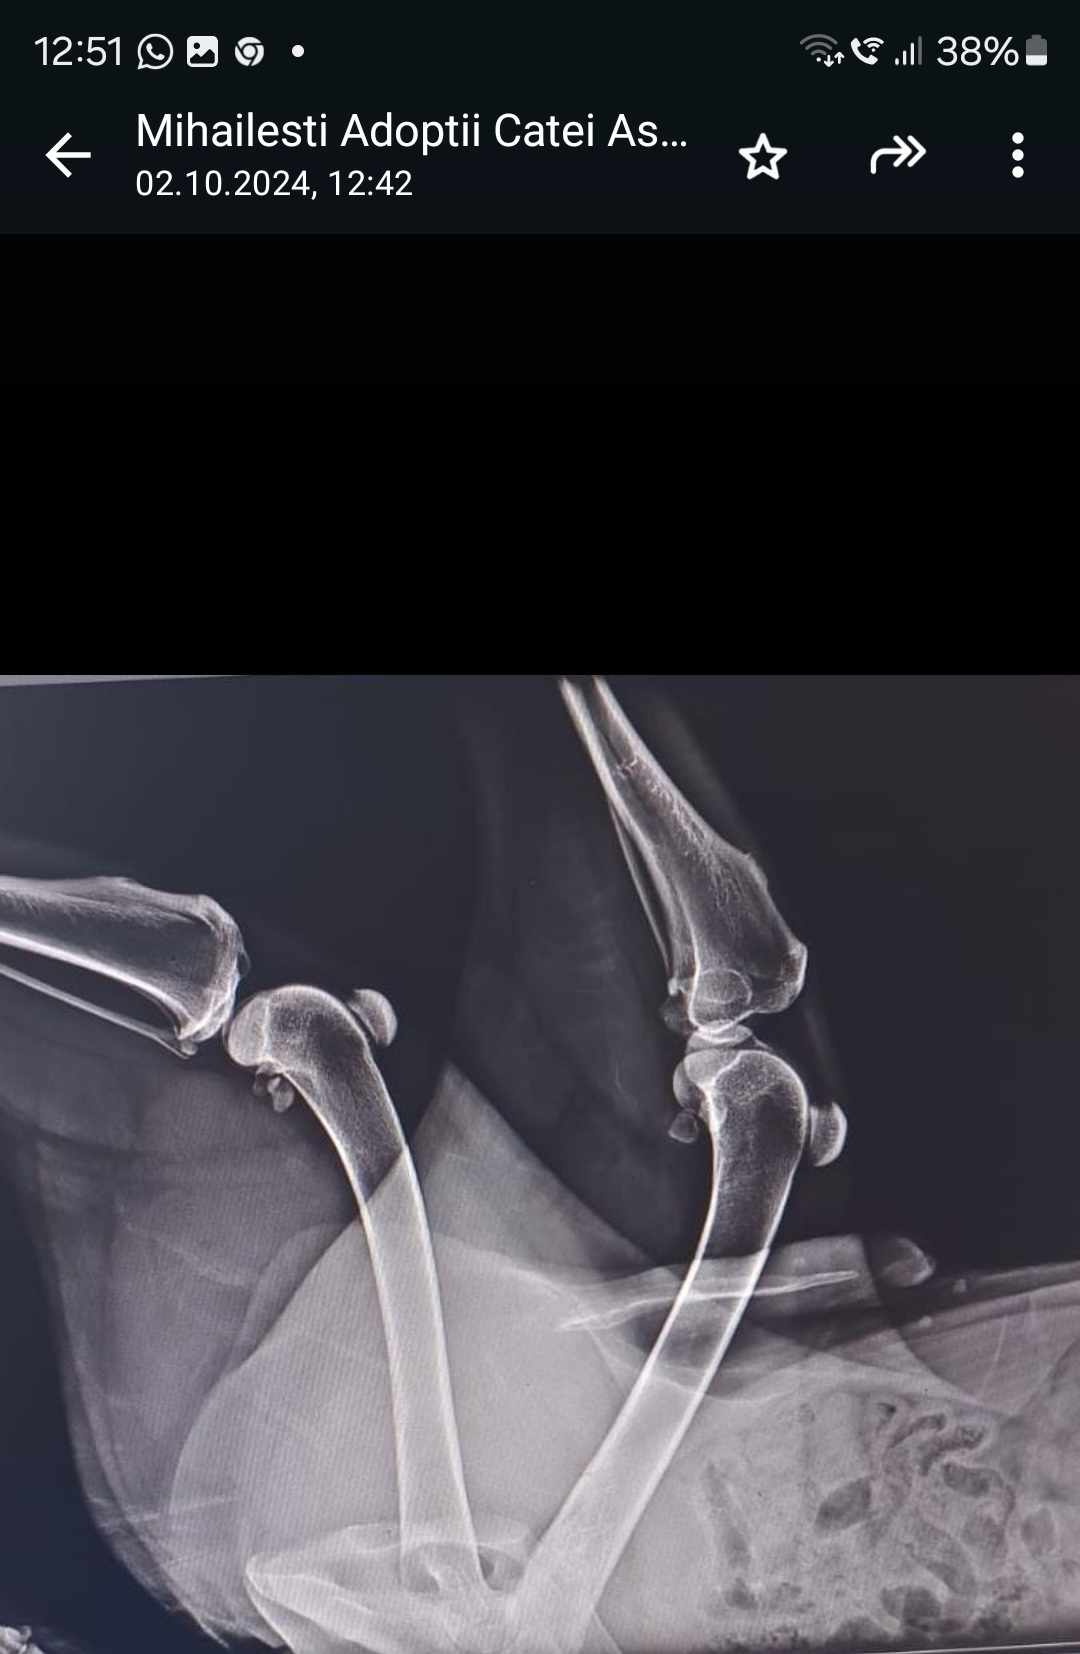

Unsere Tierschützerin entdeckte ihn im ASPA Mihailesti Shelter und bat uns im Hilfe. Wir nahmen ihn in unsere Vermittlung auf und lernten ihn bei einem Besuch dort auch selber kennen und auch lieben. Er ist mit seinen 78 cm Schulterhöhe eine wahre Erscheinung und unsere Spekulationen, ob er HSH/Wolfshund/Irgendwas ist, halten noch an. Er ist aber auf jedenfall zweierlei: Freundlich und lieb und zum zweiten leider gehandicapt. Wir haben das gewusst, Untersuchungen von Sache Vet in Bukarest hatten schon ergeben, dass der ca. 3jährige Red an einer vermutlich angeborenen Femur- Nekrose leidet. Dies geht mit üblen Schmerzen einher und wir wollten ihn deshalb nicht mehr in dem 1200 Hunde starken Shelter sitzenlassen, man hat dort einfach keine Möglichkeiten, für einen solchen Hund etwas zu tun!